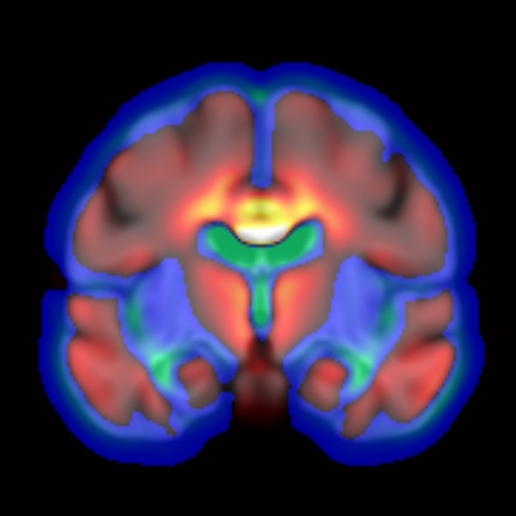

Dans le domaine de la santé, les recherches menées concernent la lutte contre le cancer, contre la maladie d’Alzheimer et contre la dengue.